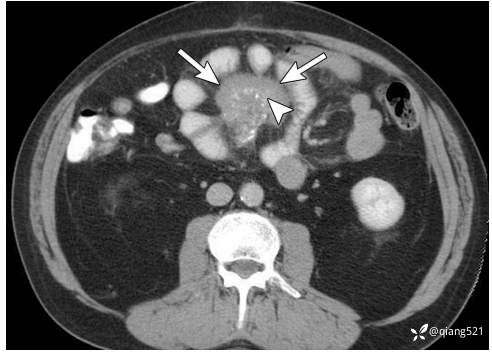

52岁男性,患有硬化性肠系膜炎。轴位增强CT显示小肠肠系膜内一分叶状软组织肿块(箭头)伴微小钙化灶(箭头),图像引导活检证实为慢性炎症。